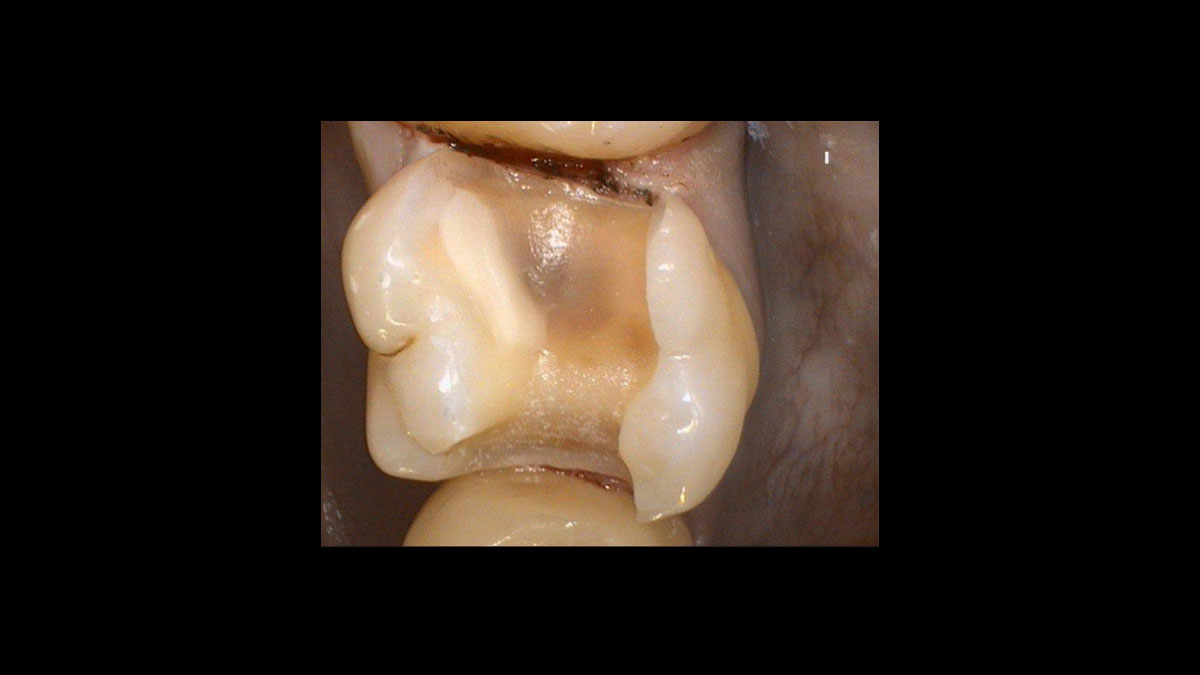

Endodoncia

Las siguientes aplicaciones se presentan en los videos y las imágenes:

• Reducción de bacterias en procedimientos endodónticos

• Reducción de gérmenes de la gangrena

Reducción de bacterias en procedimientos endodónticos